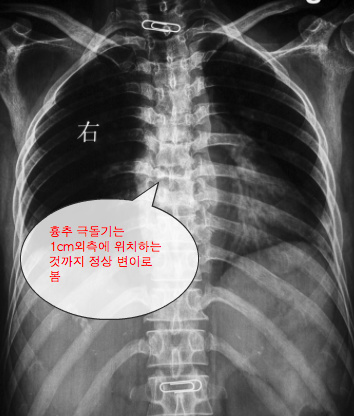

Bursae are regularly found between the neighboring lumbar and thoracic spinous processes. As with the other sections of the vertebral column, the therapist should not expect the lumbar spinous processes to always form a straight line. The lumbar spinous processes can protrude laterally away from the mid-line by up to a few millimeters and up to one centimeter in the thoracic spine and still be seen as a normal variation in anatomy.

- 치료사는 요추 극돌기가 중앙에 위치할 것으로 기대함. 실제 요추 극돌기는 중앙에서 몇 밀리미터정도 외측에 위치하고 흉추 극돌기에서 1cm떨어진 위치도 정상변이로 봄